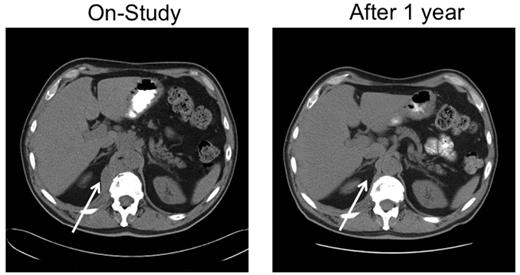

A 67-year-old man with stage IVA diffuse large B-cell lymphoma. He was treated with rituximab, cyclophosphamide, vincristine and prednisone × 6 with an initial complete response, only to relapse 7 months later. He responded to salvage chemotherapy and received an autologous stem cell transplantation with a 6-month TTP. After failing single-agent rituximab, he joined this study. He responded to tipifarnib 300 mg twice daily. Because of myelosuppression, the dose was reduced to 100 mg twice daily. He maintained remission for 25 months before progressing on therapy. Tumor biopsies before and after tipifarnib demonstrated low bcl-2 protein tumor content at baseline with a marked increase in Bim isoforms and decrease in p-ERK after tipifarnib (patient 6; Figure 2C).

Further analysis focused on signaling and expression of Bcl-2 family members. Preclinical studies have shown that tipifarnib inhibits mitogen-activated protein kinase signaling, leading to killing that is dependent on Bim up-regulation and is inhibited by high Bcl-2 in malignant human lymphoid lines.22 Analysis of paired samples obtained in this study indicated that the tipifarnib dose of 300 mg twice daily produced inhibition of HDJ-2 farnesylation, documenting FT inhibition (Figure 2C patients 3 and 5). Although effects on S6 phosphorylation, a readout of Rheb inhibition,21,28 were variable in the post-treatment lymphoma samples, tipifarnib strongly inhibited ERK phosphorylation in several lymphomas (eg, Figure 2C patients 5 and 6). Moreover, Bim increased on day 8 in 7 of 10 paired samples examined (Figure 2C; and data not shown), confirming in clinical material the change observed during tipifarnib-induced apoptosis in lymphoid lines.22 Multiple Bim isoforms increased in some cases (Figure 2C patients 5 and 11), whereas one of the shorter, more potent splice variants selectively increased in others (patients 3 and 6). On the other hand, Bcl-2 was also detectable in many of the samples tested (Figure 2D) and, when present at high levels, would be expected to override any impact of Bim up-regulation.22 Consistent with these preclinical findings, we observed 3 PRs (treatment duration 4-25 months) and 1 disease stabilization in 7 lymphoma cases with low/absent Bcl-2 at baseline but no PRs and 1 disease stabilization among 6 lymphoma cases with medium or high Bcl-2 at baseline. This trend, which did not reach statistical significance because of the small sample size, identifies Bcl-2 as a second predictive marker that should be examined further in future clinical trials of tipifarnib in lymphoma.